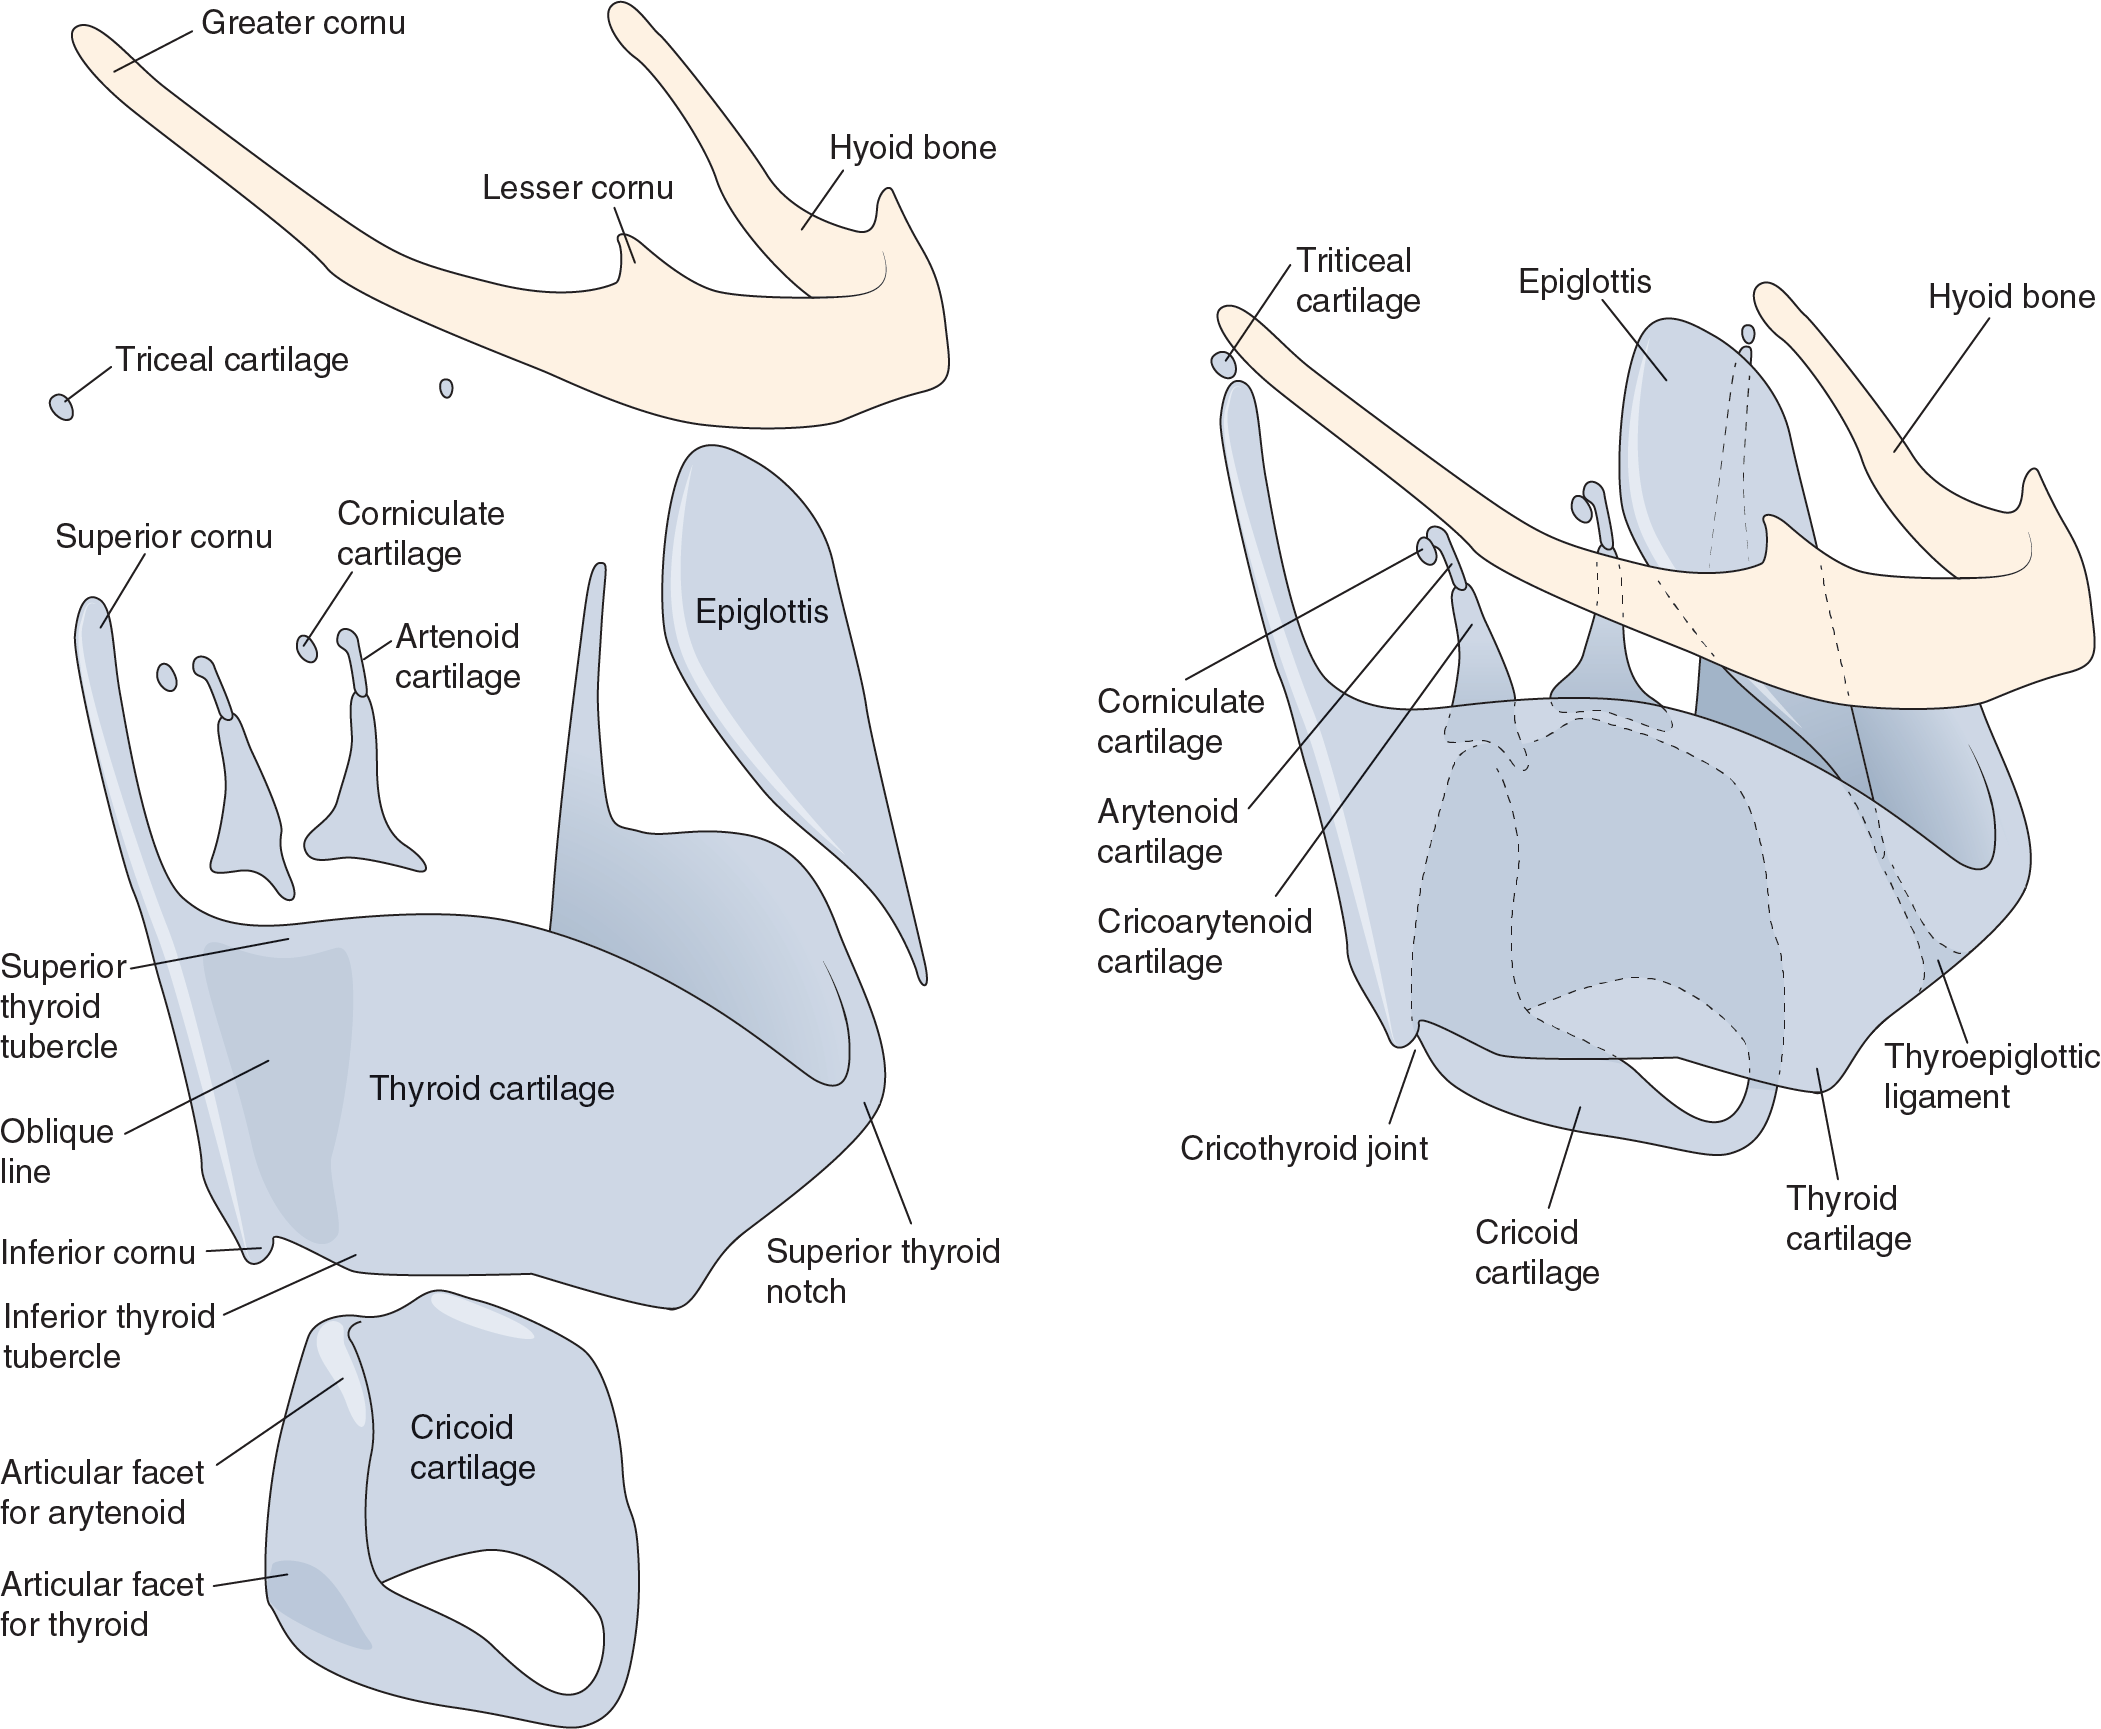

Medical Illustration

All images are works made for hire and are the exclusive property of the client. These are shown as sample purposes of my work only. For licensable work, please see my Illustration Services page.

Medical Illustrator for Precision Graphics, Lachina, and Human Kinetics Publishing (current)

Contract freelancer for many others, some examples of my work below.